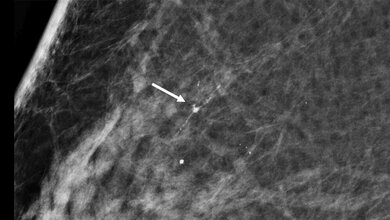

Chirurgische Behandlung des primären Mammakarzinoms

Wegen eines Verdachts auf Brustkrebs haben Ärztinnen und Ärzte im Jahr 2014 bundesweit 74.224 chirurgische Eingriffe in 817 Kliniken durchgeführt. Im Allgemeinen kann bei der chirurgischen Behandlung des Mammakarzinoms zwischen der Durchführung eines brusterhaltenden Verfahrens und einer Entfernung der Brust unterschieden werden. Die Wahl des therapeutischen Verfahrens ist neben den Eigenschaften des Tumors abhängig von der individuellen körperlichen, psychischen und sozialen Situation sowie dem Alter, den Begleiterkrankungen und den Präferenzen der Patientin oder des Patienten.